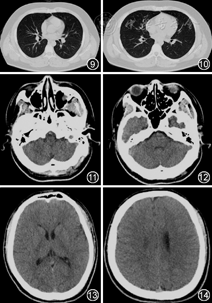

病例2 患者男,20岁,2020年3月24日从英国回国隔离,2020年3月28日出现发热,体温最高37.7 ℃,自诉咽部异物感,3月29日于外院查白细胞4.41×109/L,中性粒细胞百分比为60.7%,淋巴细胞绝对值为1.12×109/L,C反应蛋白为7.11 mg/L,鼻、咽拭子新型冠状病毒核酸均为阳性,遂于3月30日转入我院治疗。患者既往有扁桃体切除病史,入院后体检:体温 37.2 ℃,脉率 82次/min,呼吸频率 20次/min,血压 142/92 mmHg(1 mmHg=0.133 kPa),SpO2为 99%(未吸氧状态),神志清楚,咽部充血,双肺呼吸音粗,未闻及明显干湿性啰音,心、腹未见异常。胸部CT示双肺间质纹理增粗,初步诊断:新型冠状病毒肺炎。给予阿比多尔片0.2 g,3次/d,口服抗病毒、乙酰半胱氨酸片600 mg,2次/d口服对症治疗。入院后胸部CT如图9,10。

患者入院后第14天出现鼻塞,体温不高,无其他阳性症状。隔日仍有鼻塞,新冠病毒核酸检测回报阳性。入院第19天患者自诉嗅觉减退,追问患者鼻塞症状开始时即出现嗅觉减退,予加用甲钴胺0.5 mg,3次/d,口服营养神经治疗。并请耳鼻喉科会诊,给予维生素B1 10 mg,3次/d,口服、维生素B12 0.1 mg,1次/d,肌肉注射营养神经,每天自行75%的酒精测试恢复情况,副鼻部CT(图11,12)提示左侧上额窦黏膜下囊肿,双侧筛窦黏膜增厚,头颅CT(图13,14)未见明显异常。再次请耳鼻喉专家会诊后,加用牛痘疫苗接种家兔炎症皮肤提取物8 U,2次/d,肌肉注射治疗。入院第24天患者自诉嗅觉较前有所好转,第30天自诉嗅觉恢复。入院第31、32天咽拭子新型冠状病毒核酸阴性,出院观察。出院后电话随访,患者嗅觉于出院后半个月完全恢复正常。后未再出现嗅觉障碍。